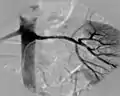

آنژیوگرافی کرونری

با پرتو ایکس میتوان تصاویری تهیه کرد که اطلاعات بسیار مفیدی را راجع به وضعیت سرخرگهای قلبی ارائه میدهد.

در این روش با یک کاتتر، مواد کنتراستزا مستقیماً به شرایین کرونر تزریق میشوند، و بلافاصله تصاویر اخذ میگردند. از این روش بخصوص زمانی استفاده میگردد که پزشک احتمال عمل جراحی قلبی را در بیمار پیشبینی میکند.